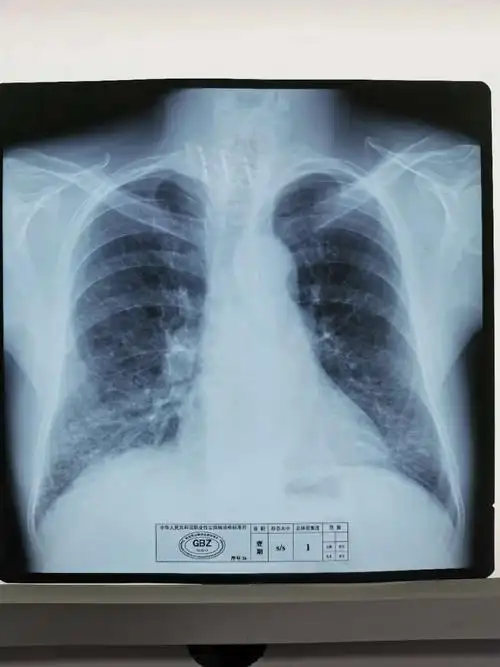

职业病尘肺标准片(照片)